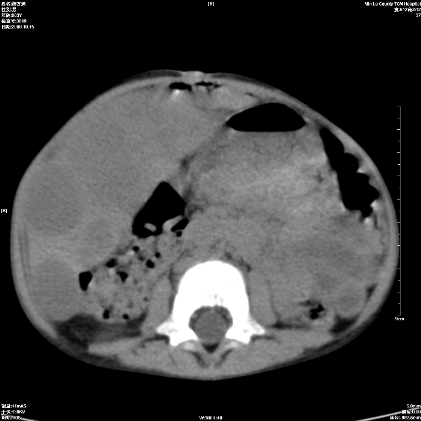

标题: PED1609:男性,3岁。彩超示肝Ca.

考虑后纵隔恶性畸胎瘤伴肝内多发转移可能性大,右侧肾上腺转移不除外.

3岁;肝低密度灶;有钙化;有转移灶;考虑肝母细胞瘤;查afp

考虑后纵隔恶性畸胎瘤伴肝内多发转移可能性大,右侧肾上腺转移不除外

考虑后纵隔恶性畸胎瘤伴肝内多发转移可能性大,右侧肾上腺转移.